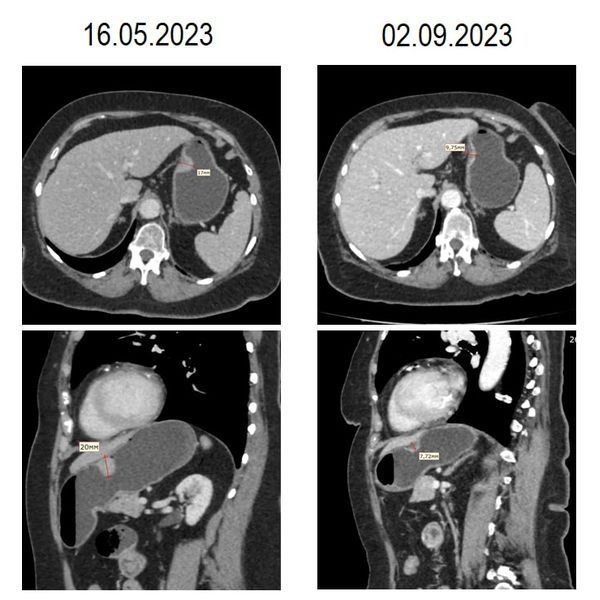

16 мая пациент также сделал компьютерную томографию (КТ) с контрастированием. Она показала образование размером 31 × 21 × 23 мм, которое росло внутрь полости желудка, и признаки парагастральной лимфаденопатии — увеличенные лимфоузлы рядом с желудком.

КТ от 2 сентября показала, что за эти 2 месяца опухоль существенно уменьшилась, подозрительных лимфоузлов не было.